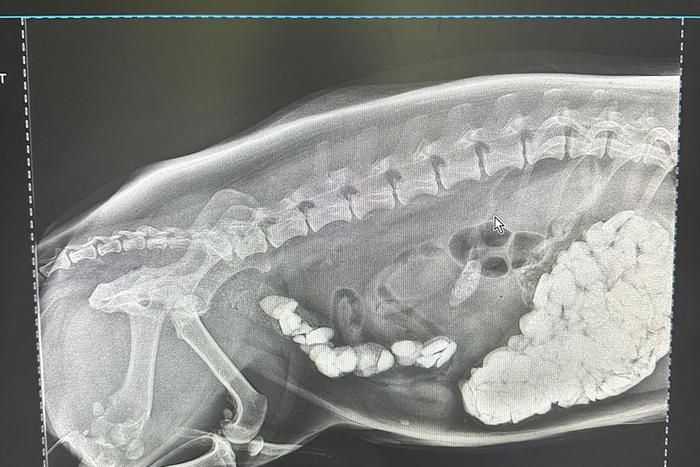

Целую миску щебня извлекли из корги ветеринары в Москве

Целую миску щебня извлекли из корги

ветеринары в Москве

2 окт. 2023

Столичный ветеринар спасала корги, который наелся щебня

Столичный ветеринар спасала корги,

который наелся щебня

22 сент. 2023